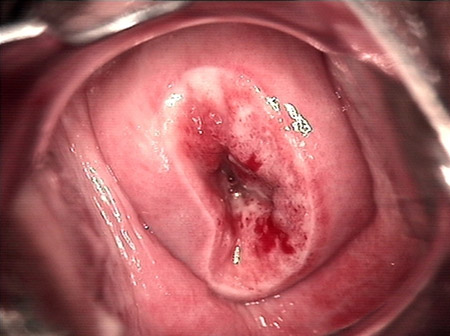

婦科leep錐切手術 CIN2-3

• CIN 2-3 修復后(圖2)CIN 2-3 修復后(圖2)